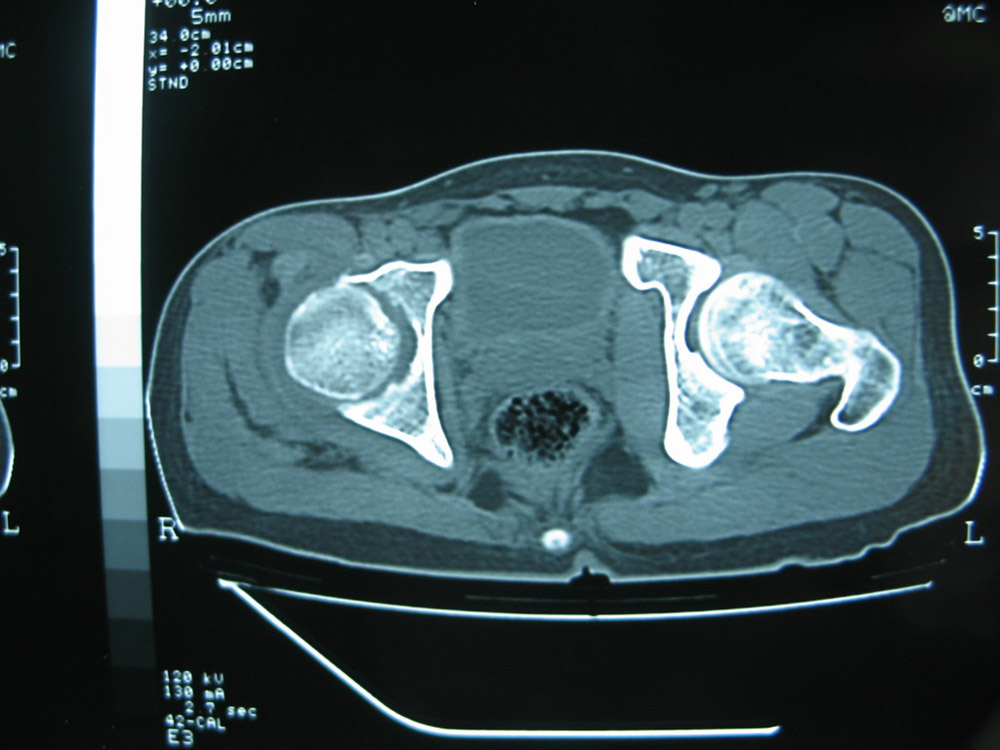

以下是引用卜一在2007-1-25 16:33:00的发言:[br]右侧髋关节股骨头及髋臼骨骨小梁疏松 粗糟,股骨头外形毛糟,软组织似肿胀,间隙略变窄.考虑:1 髋关节结核可能性大.2 缺血性坏死?3 化脓性髋关节炎?

以下是引用hhcckk在2007-1-25 17:18:00的发言:[br][br]支持髋关节结核,[br]依据关节面破坏,有脓肿,脓腔内有钙化,关节周围增生不明显,鉴别[br]1化脓性的病变增生明显,临床上有高热[br]2创伤引起的关节炎,无菌坏死不会引起关节面的破坏,而且不会在这么短的时间内出现[br]